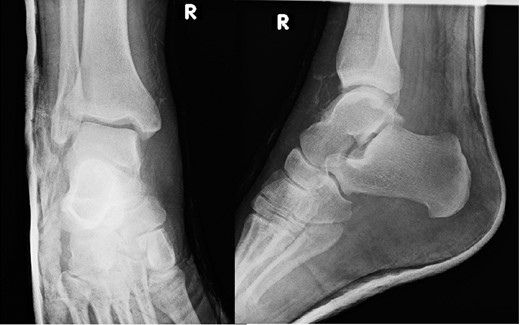

A 30-year-old male patient presented to Emergency Department (ED) following a run over injury. The patient described the mechanism of injury as moving his body over his run over foot. On clinical examination, there was obvious deformity and swelling of the right ankle. Dorsalis pedis pulse was felt but weak compared to the contralateral side with a capillary refill time under 3 s. The posterior tibial artery could not be palpated because of the deformity. X-rays showed posterior ankle dislocation without associated fractures (Fig. 1). Urgent reduction of the dislocation was done under sedation in ED. The knee was first flexed to relax the tendon Achilles then longitudinal traction with gentle forward force applied to the heel with immediate reduction of the deformity achieved. The foot was reassessed for vascular status. Triphasic pulse in both drosalis pedis and posterior tibial artery was detected with hand held Doppler. Ankle was immobilized in posterior below knee back slab to accommodate for swelling and check x-rays confirmed reduction of the ankle joint (Fig. 2). CT scan was done afterwards to define any subtle incongruity or osteochondral fragments entrapped in the joint. CT did not show any associated fractures and showed congruent reduction of the ankle joint (Fig. 3). Patient was mobilized touch weight bearing for first 2 weeks. The back slab was changed for weight bearing short leg cast and progressive weight bearing was allowed for the following 4 weeks. At 6 weeks follow up, plaster was removed and on examination patient still had moderate tenderness over the medial joint line and deltoid ligament area. Also, patient had limited range of plantar and dorsal flexion. Referral for physiotherapy was done for start of functional rehabilitation and range of motion exercises and in mean time MRI was done to delineate extent of ligamentous injury. MRI showed bone bruising of the lateral malleolus, medial malleolus and lateral talus (Fig. 4). The anterior talufibular ligament (ATFL), calcaneofibular ligament (CFL), posterior talofibular ligament (PTFL) and deltoid ligaments were sprained but intact. At 12 weeks follow up, patient could walk normally without any symptoms of instability and achieved 20° of both plantar and dorsal flexion. At 16 weeks, patient achieved full range of motion of ankle and was able to return to work. At 24 weeks follow up patient was able to resume his sport activates as preinjury level.

T2 MRI images showing high signal in medial malleolus, lateral malleolus and talus signifying bone bruise.